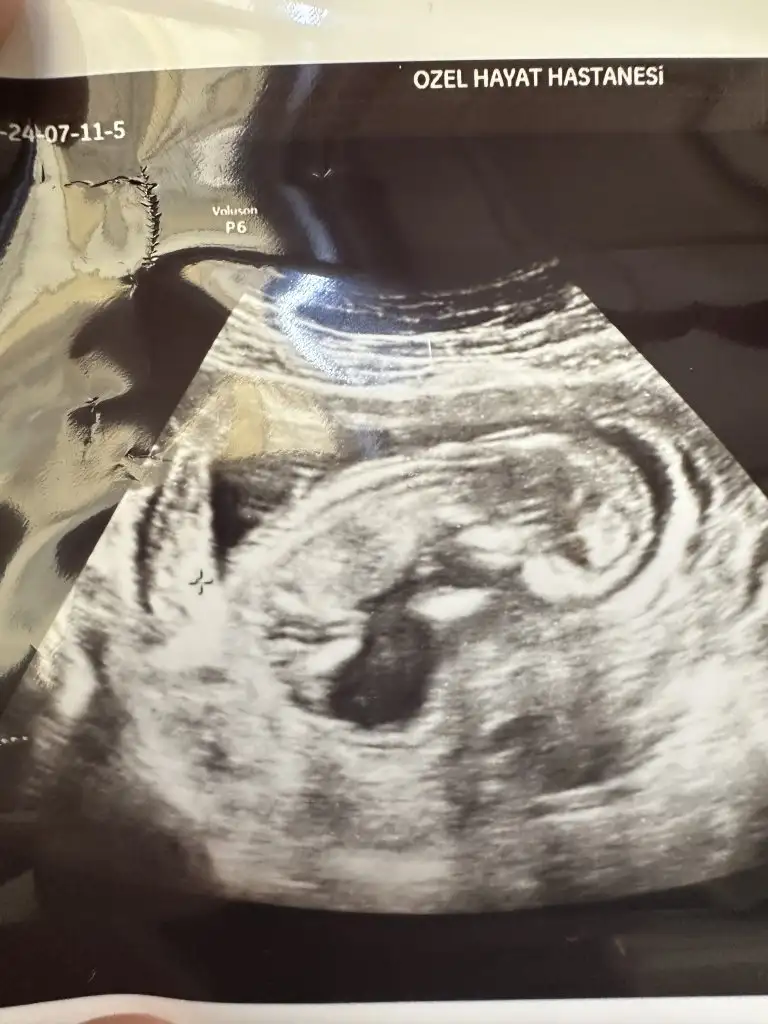

Az önce çekildik. 12+0 ız. Cinsiyet tahminleri nedir arkadaşlar?

• IMG_20240711_222412.webp

IMG_20240711_222412.webp

18,1 KB · Görüntüleme: 71

• IMG_20240711_222407.webp

IMG_20240711_222407.webp

17,7 KB · Görüntüleme: 75

• IMG_20240711_222357.webp

IMG_20240711_222357.webp

18 KB · Görüntüleme: 65